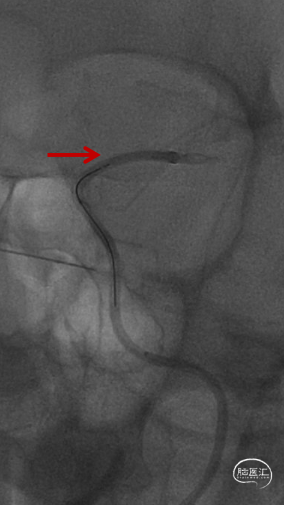

复查造影远端仍然闭塞,负压状态上行SKATHI远端通路导管回收保护伞并抽吸血栓,可见保护伞及大量血栓取出,复查造影C3段仍有血栓。再次上行SKATHI远端通路导管抽吸取栓,复查造影示远端血流通畅。

等待10分钟,复查造影颈内动脉及远端分支通畅,结束手术。DynaCT左侧外囊区域少许造影剂渗出。

4. 6F 115cm SKATHI远端通路导管通过性高,能够轻松抵达大脑中动脉实现SWIM技术取栓。抽吸能力及抗疲劳能力强,本次术中采取了四次的抽吸治疗,均轻松胜任,值得信赖。